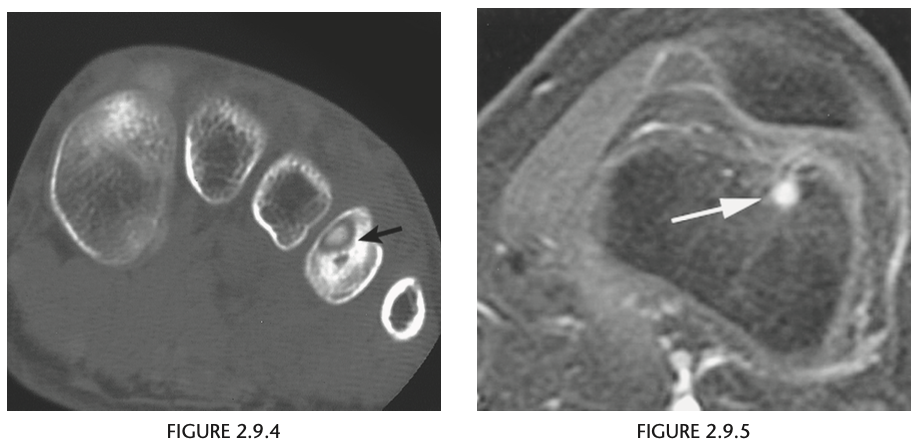

A 34-year-old man with sudden onset of calf pain during a tennis match

Sagittal fat-suppressed proton-density MRI of the lower calf (Fig. 2.29.1) demonstrates increased signal intensity at the musculotendinous junction of the Achilles tendon (arrows). An axial fat-suppressed proton-density image through this area reveals a mass of increased signal intensity in the expected location of the Achilles tendon (Fig. 2.29.2, arrow) Achilles tendon tear, full thickness Radiographs may support the clinical diagnosis by showing marked soft-tissue swelling behind the distal tibia and ankle and obliteration of the pre-Achilles fat pad. Ultrasonography can reliably show the degree of tendon injury. MRI features of a partial tear of the Achilles tendon in- clude tendon enlargement, discontinuity of some of the tendon fibers, intratendinous areas of increased signal intensity on T2-weighted or ­ inversion-recovery sequences, and surrounding soft-tissue edema. In the complete Achilles ten- don rupture, an intratendinous gap is present and is generally filled with high-signal-intensity blood and edema.